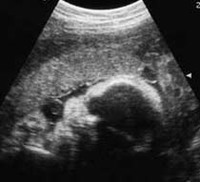

Ecografía 4D, ¿qué tener en cuenta antes de contratarla?

EmbarazoEn entradas anteriores hemos hablado de la gran revolución que ha supuesto la ecografía para los controles prenatales y la novedad de la ecografía 4D, una ecografía tridimensional que añade el componente de poder ver al bebé en...